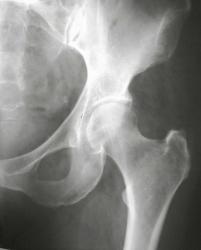

Mario, show the mormal MRI-picture for comparison

Слева отмечается повышение сигнала от костного мозга; справа костный мозг гипоинтенсивен (норма при использовании посследовательней с подавлением сигнала от жира)

Let me see...